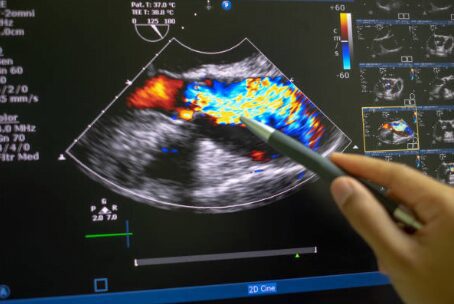

When it comes to diagnosing heart conditions, precision and reliability are key. At AMIS, we understand the importance of advanced diagnostic tools in healthcare. The Doppler test for the heart, also known as Doppler echocardiography, uses sound waves to evaluate the movement of blood through your heart and blood vessels. This non-invasive test provides vital information about the flow of blood, helping to diagnose various cardiac conditions. Stay with me as we delve deeper into how this technology could be pivotal in heart healthcare.

This technique utilizes ultrasound waves that bounce off the circulating blood cells in the heart. When these ultrasound waves return to the machine, they do so at different frequencies, depending on how fast the blood is moving and in which direction. This effect is similar to the change in pitch heard from a passing siren and is known as the Doppler effect.

A Doppler test can provide a wealth of information, including the speed and direction of blood flow through the heart’s chambers and valves. This is crucial for identifying conditions like heart valve stenosis or regurgitation (leaky valves), which can lead to serious heart complications if not addressed.